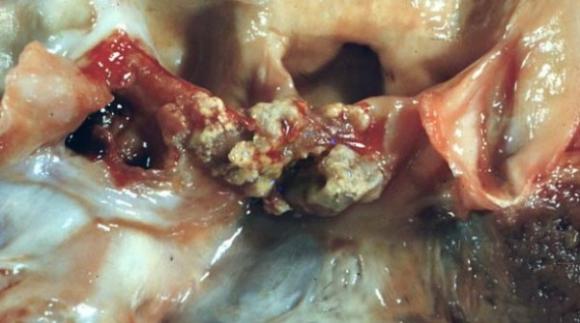

Médicos argentinos desarrollan una nueva técnica que permite un rápido diagnóstico que evita afecciones cardíacas

Problemas que genera la inflamación interna del corazón podrán evitarse mediante una nueva técnica desarrollada por médicos argentinos. La nueva técnica consiste en un método de diagnóstico rápido para la...